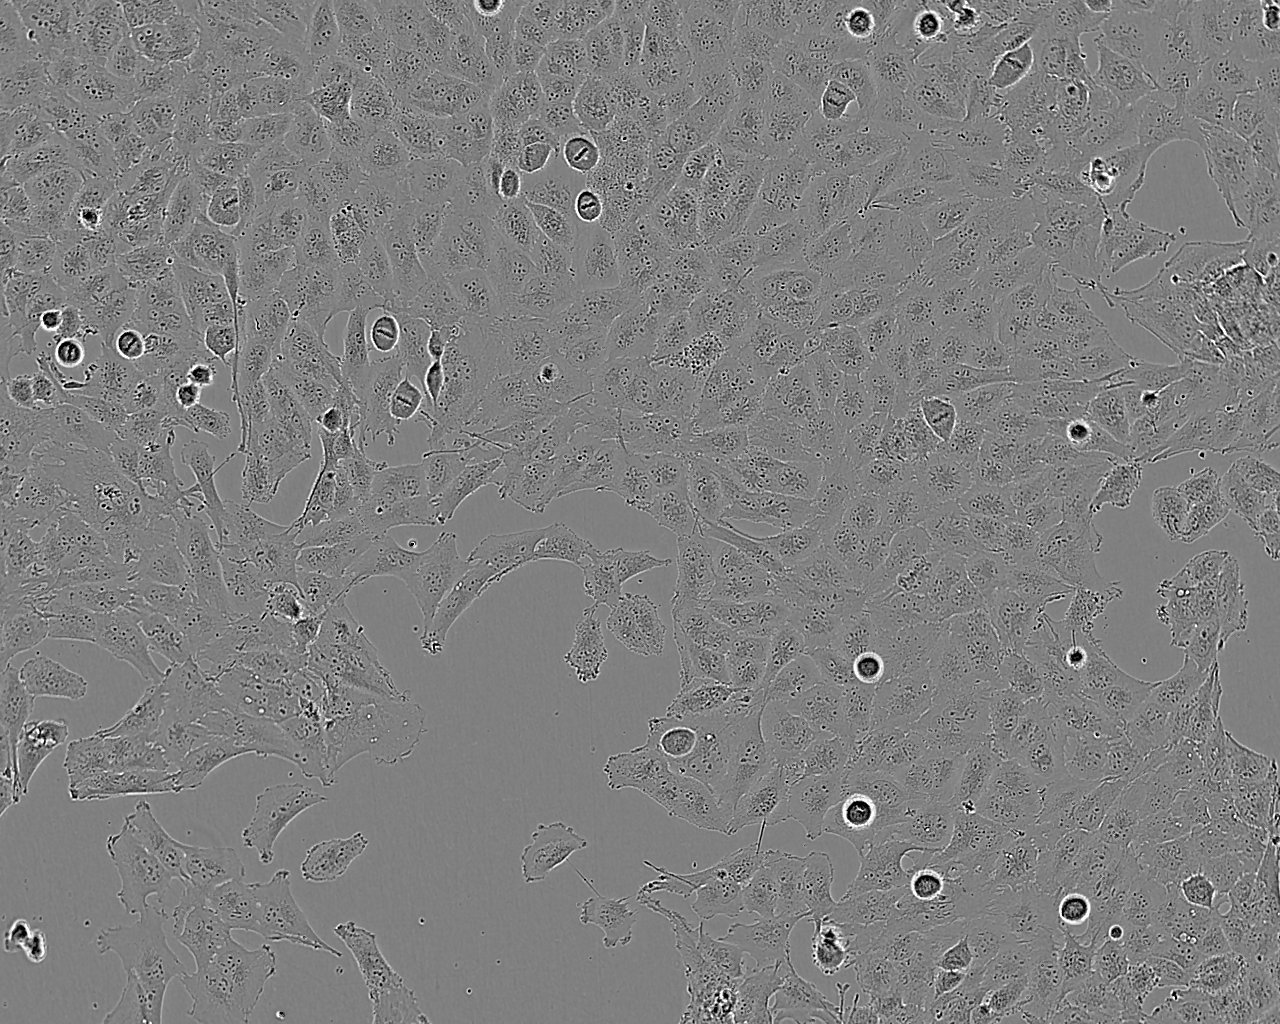

形态特征 成纤维细胞样

生长特征 贴壁